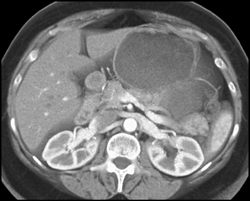

Diagnosis

Intraductal Papillary Mucinous Neoplasm (IPMN)